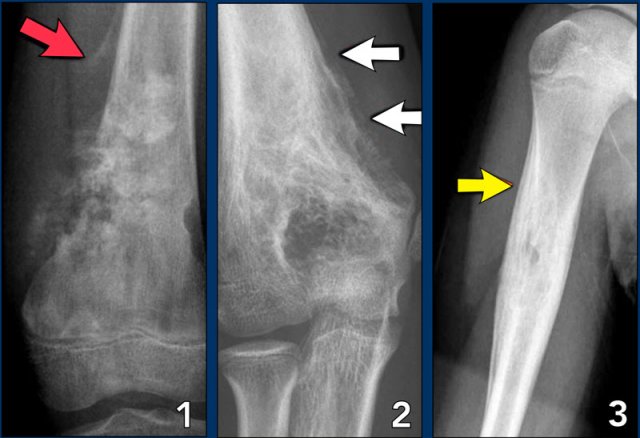

Aggressive periosteal reaction Aggressive periosteal reaction

Aggressive periosteal reaction (2)

1. Osteosarcoma with interrupted periosteal rection and Codman's triangle proximally (red arrow).

There is periosteal bone formation perpendicular to the cortical bone and extensive bony matrix formation by the tumor itself.

2. Ewing sarcoma with lamellated and focally interrupted periosteal reaction. (white arrows)

3. Infection with a multilayered periosteal reaction.

Notice that the periostitis is aggressive, but not as aggressive as in the other two cases.